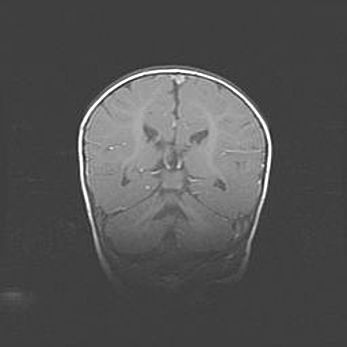

Наружная гидроцефалия с возможной атрофией височных областей.

Возраст: 28 дней

Вес: 3670 г

Пол: мужской

Окружность головы: 38 см

Срок гестации: 40 недель

Гидроцефалия головного мозга у новорожденных – это заболевание, которое характеризуется скоплением избыточного количества спинномозговой жидкости в желудочковой системе головного мозга в результате затруднения её перемещения от места выработки к месту поглощения в кровеносную систему или вследствие нарушения абсорбции. При открытой наружной форме гидроцефалии у новорожденных расширяются и переполняются субарахноидные пространства.

При нормотензивных  формах,  которые,  как  правило,  являются  следствием  перенесенных ишемических  повреждений  паренхимы  мозга,  возможно  сочетание микроцефалии  с нормотензивной гидроцефалией. В основе данных изменений лежит атрофия больших полушарий с преимущественной  локализацией  в  лобно-височных  областях.